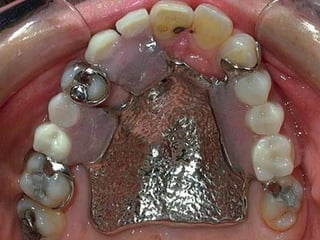

Classification according tosupport The partial dentures are classified according to the vertical support into I-Tooth borne; derives its support totally from the abutment teeth throughout rests. 2-Mucosa borne; supported totally by the edentulous ridge. 3-Tooth-mucosa support; supported by both abutment teeth and the edentulous ridge as in free end saddle (distal extension base(.

Class IV Single bilateraledentulous area located anterior to the remaining natural teeth